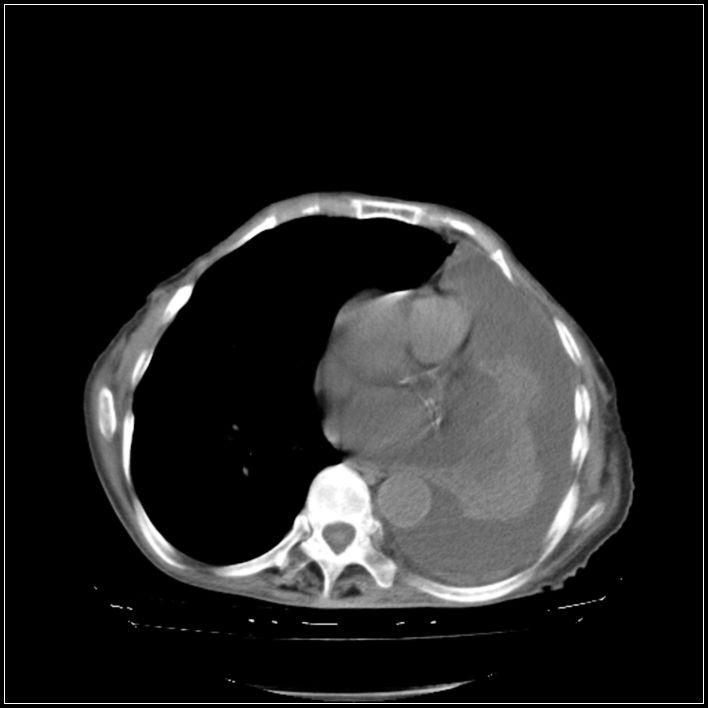

以下是引用影象小辈在2008-5-31 16:25:00的发言:[br]左侧胸腔团状不规则致密影,界欠规整,密度不均匀,其内可见更低密度影及高密度影,并可见包裹性胸腔积液 考虑为1.畸胎瘤 2.肺癌